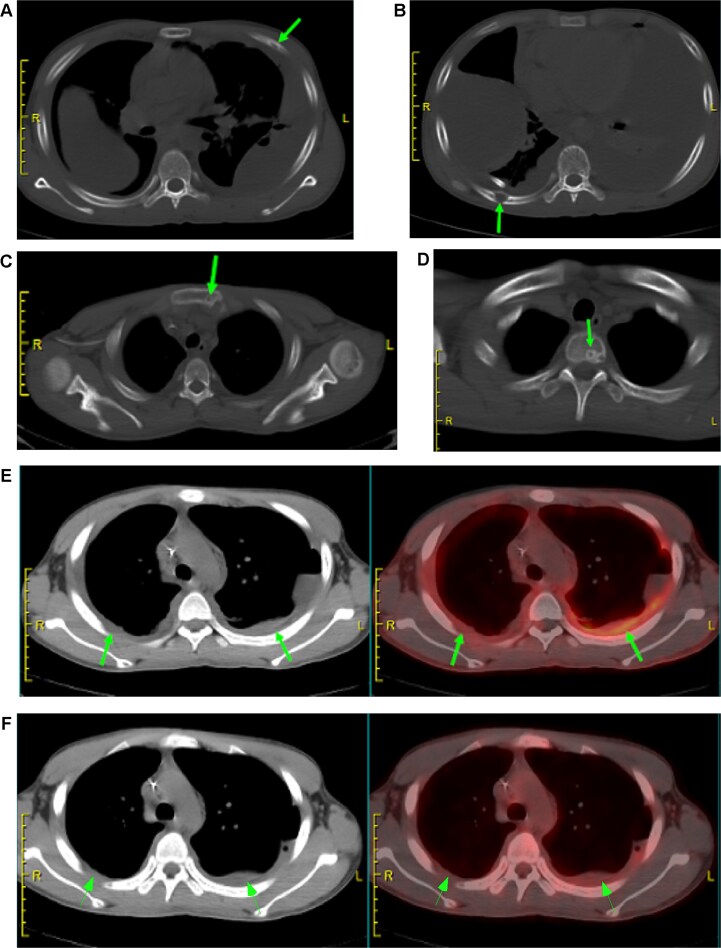

一例年轻男性Gorham-Stout综合征(GSS),一种罕见的导致骨质流失的淋巴血管疾病,表现为咳嗽、呼吸困难和乳糜胸膜积液感染金黄色葡萄球菌。尽管进行了胸导管结扎术,他的乳糜胸还是复发了。影像学显示胸骨和肋骨病变,胸膜增厚。肌电图显示轻度双侧膈神经运动传导异常。一年后,他出现了有症状的左侧膈疝并伴有部分肠梗阻,需要手术修复。本病例强调了GSS合并乳糜胸患者早期膈肌监测的必要性,以防止严重的并发症。

A young male with Gorham-Stout syndrome (GSS), a rare lymphovascular disorder causing bone loss, presented with cough, difficulty breathing, and chylous pleural effusion infected with Staphylococcus aureus. Despite thoracic duct ligation, his chylothorax recurred. Imaging showed bone lesions in the sternum and ribs, along with thickened pleura. Electromyography revealed mild bilateral phrenic nerve motor conduction abnormalities. A year later, he developed a symptomatic left diaphragmatic hernia with partial bowel obstruction that required surgical repair. This case highlights the need for early diaphragm monitoring in GSS patients with chylothorax to prevent serious complications.